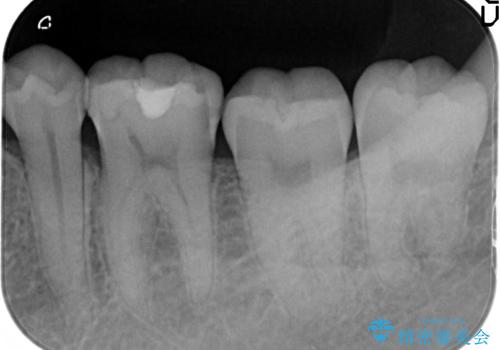

- 虫歯の検診を求めて来院されました。

X線検査により外から見てもわからない虫歯が認められたので、マイクロスコープ下で丁寧かつ徹底的に虫歯を除去しセラミックインレーによる修復を計画します。